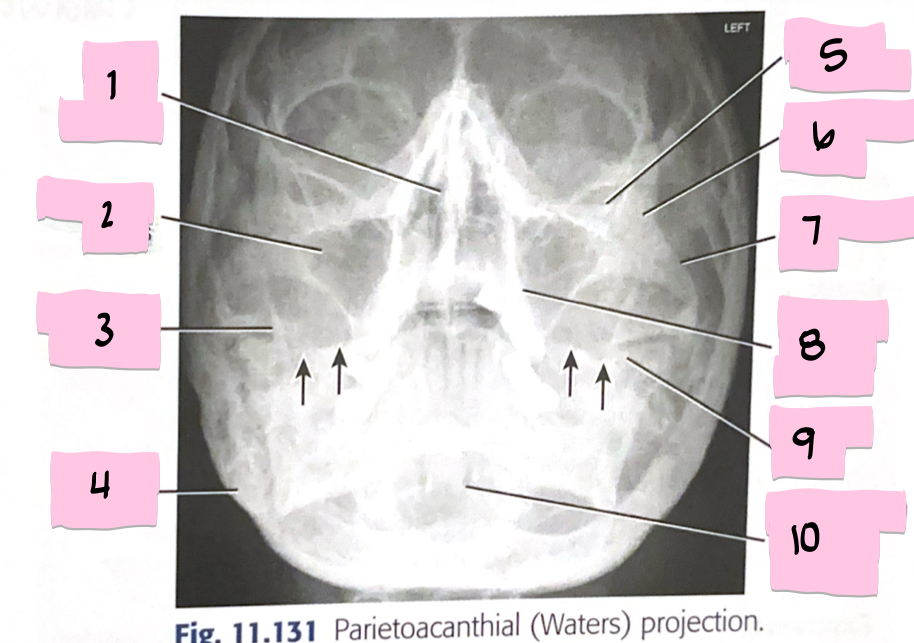

What is 1 pointing to?

Bony nasal septum

What is 2 pointing to?

Maxillary sinus

What is 3 pointing to?

Coronoid process

What is 4 pointing to?

Mastoid process

What is 5 pointing to?

Inferior orbital rim

What is 6 pointing to?

Zygomatic bone

What is 7 pointing to?

Zygomatic arch

What is 8 pointing to?

Maxillary alveolar process

What is 9 pointing to?

Petrous ridge

What is 10 pointing to?

Dens within foramen magnum